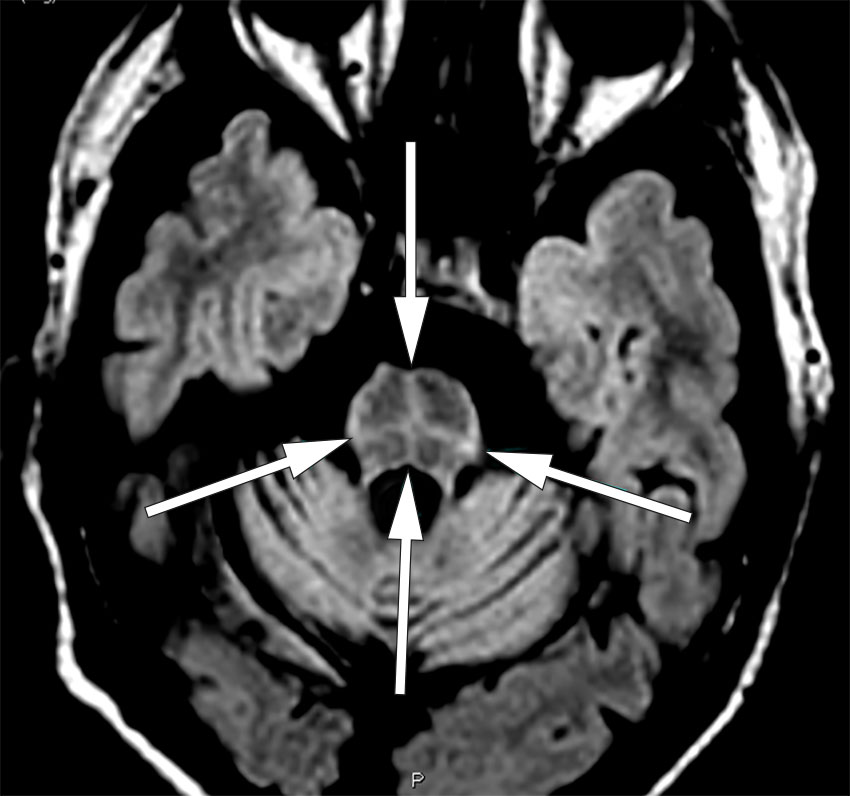

Transversalt MR-bilde med FLAIR-sekvens viser, i tillegg til generell cerebellar atrofi, et korsformet hyperintenst signal i pons, såkalt korsbolletegn (på engelsk: hot cross bun sign).

Som ledd i utredningen ble det tatt MR caput, som viste korsformet hyperintenst signal i pons, patologisk signal i de midtre cerebellare pedunkler og generell cerebellar atrofi. Supplerende PET-undersøkelser med FDG (2-[18F]fluoro-2-deoksy-D-glukose) viste lavt opptak i cerebellum og pons. Dopamintransporterskanning viste normalt opptak i striatum. Basert på anamnese og bildediagnostiske og kliniske funn fikk pasienten diagnosen multisystematrofi, cerebellar variant.

Korsbolletegn refererer til et karakteristisk korsformet hyperintenst signal i pons på transversale MR-bilder med T2-vekting eller FLAIR-sekvens (fluid-attenuated inversion recovery). Navnet kommer fra et bakverk som på norsk kalles korsbolle (eng. hot cross bun). Man antar at funnet skyldes selektivt tap av transversale pontocerebellare fibre og pontine nevroner, med utsparing av pontine tegmentum og kortikospinale baner (2). Hos mer enn 60 % av pasientene med multisystematrofi av cerebellar variant ses dette MR-funnet innen to år etter symptomdebut (1). Tidligere har man ment at korsbolletegn har vært patognomonisk for multisystematrofi, men funnet kan også foreligge ved andre nevrodegenerative sykdommer som hereditær cerebellar ataksi og demens med lewylegemer (3), og ved visse metabolske og inflammatoriske tilstander (4).